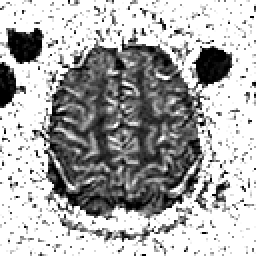

Alzheimer's Disease: SPECT/fMRI overlay -- Slice #8

Keith A. Johnson (keith@bwh.harvard.edu), J. Alex Becker (jabecker@mit.edu)